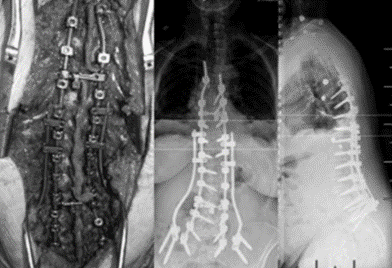

图5 脊柱远端融合节段越多,如包括L5-S1水平固定到骶骨或髂骨,发生交界性后凸的可能性越大

(2)上固定椎在交界区或存在交界性后凸

图6 长节段融合固定上固定椎(UIV)选择在胸10-12胸腰椎交界区是PJK的风险因素之一

图7 术前-术后1个月-术后1个月外观